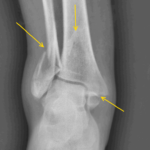

Пяточная шпора, или подошвенный фасциит

Для этой патологии характерно появление болезненных ощущений в пятке воспалительного происхождения. Причинами развития пяточной шпоры становятся растяжение или длительное травмирование наростом подошвенной фасции пяточной кости. Обычно это результат долгого нахождения на ногах, плоскостопия или повреждения костных структур стопы. Фасция воспаляется, провоцируя формирование костного нароста. А он, в свою очередь, постоянно ее травмирует. Такой замкнутый круг приводит к появлению болей нее только при ходьбе, но и в состоянии покоя.

Из-за многочисленности и разнообразия причин болей в пятке первичный диагноз редко выставляется на основании жалоб пациента и его внешнего осмотра. Проводятся общеклинические исследования крови, позволяющие выявить анемию или лейкоцитоз. Результаты биохимических анализов помогут исключить или подтвердить аутоиммунные патологии. Также проводятся следующие инструментальные исследования:

- ренгенография голеностопного сустава, костей стопы в двух проекциях;